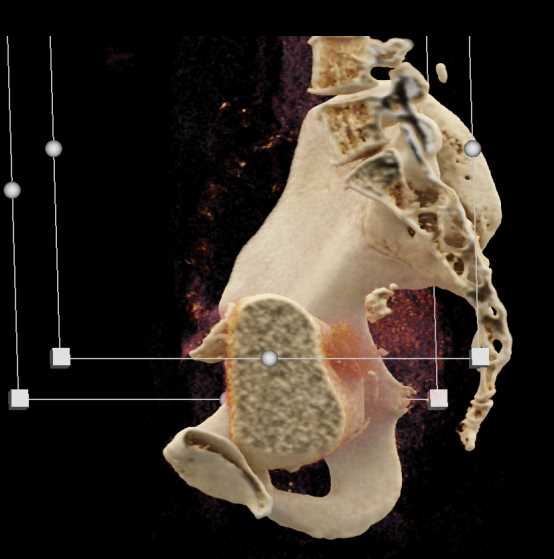

Urachal Carcinoma of the Bladder